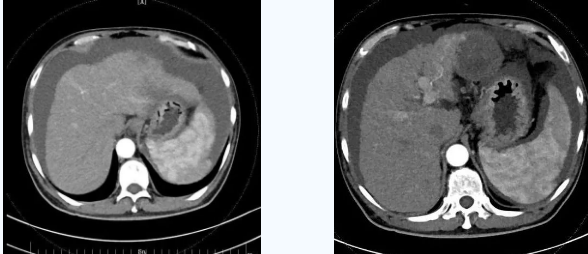

術后一個月秦先生來院復查,腹水已明顯較前減少,精神和飲食較術前明顯好轉。

韓國宏院長介紹,TIPS原理是采用特殊的介入治療器械,在X線透視導引下,經頸靜脈入路,建立肝內的位于肝靜脈及門靜脈主要分支之間的人工分流通道,并以金屬覆膜內支架維持其永久性通暢,達到降低門脈高壓后減少腹水產生,控制和預防食道胃底靜脈曲張破裂出血的目的。